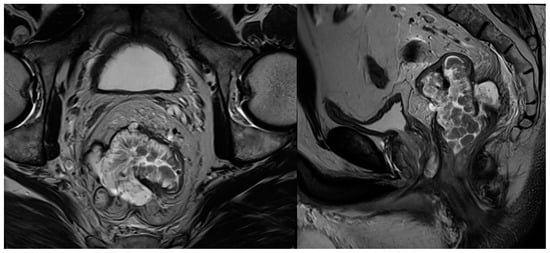

2.6. Mucinous Tumours

| Mucinous tumours | Mucin component is readily identified as high signal intensity on T2WI |